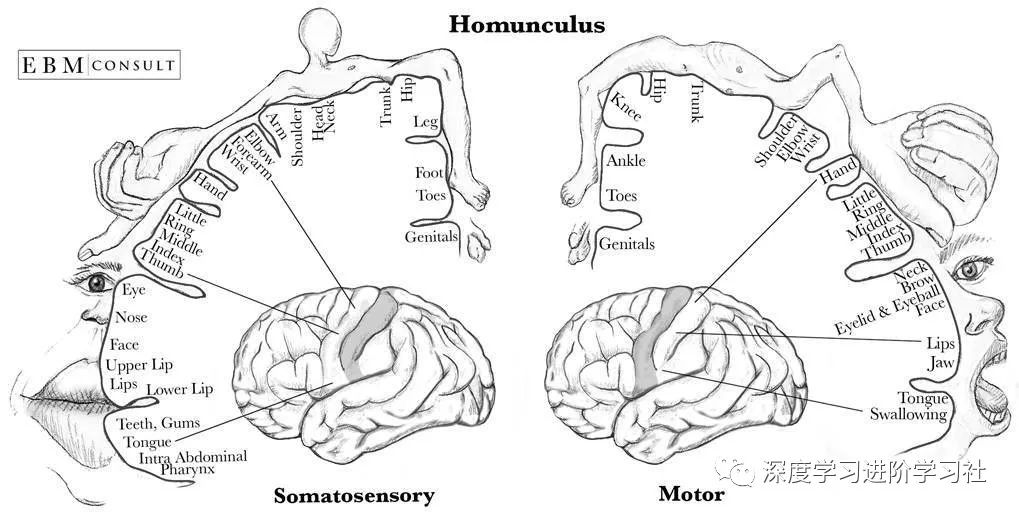

运动和躯体感觉皮层紧挨着对方,它们很有趣,因为它们已经被良好的映射出来了。神经科学家确切地知道每个部分连接到你身体的哪一个部分。于是就有了下面这张令人毛骨悚然图:侏儒。

由先锋神经外科医生怀尔德·彭菲尔德创建的侏儒,在视觉上显示运动和躯体皮层如何被映射。